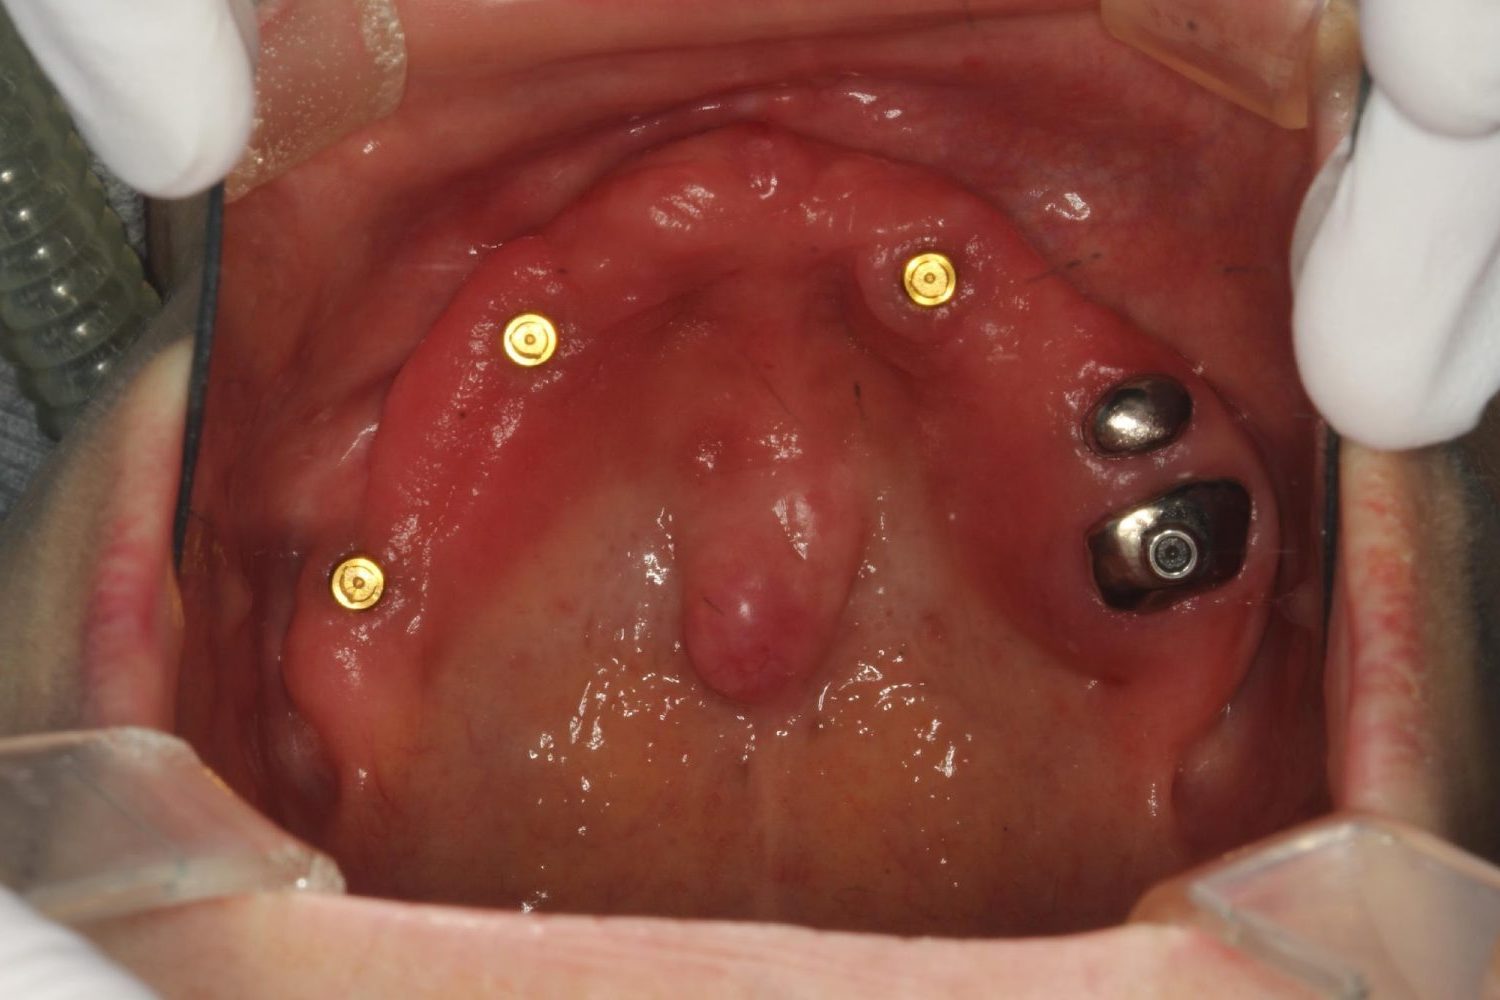

インプラント治療の症例紹介⑦

Before

治療中

After

主訴

歯肉の腫脹、安定した入れ歯を入れたい

治療内容

上顎に5本インプラント埋入を行いIOD。下顎は固定性を希望したので3本埋入し上部構造を装着しました。

治療費

3,377,000 円(税込)

治療期間

21ヶ月

通院回数

27回

想定されたリスク

※義歯を安定させるためのインプラントなので、顎堤が吸収等起こし裏装が必要になる可能性がありました。

濱 仁隆先生

浜歯科

上顎をロケーターアタッチメントにより義歯を安定させる事を可能にし、コストも下げられた症例。